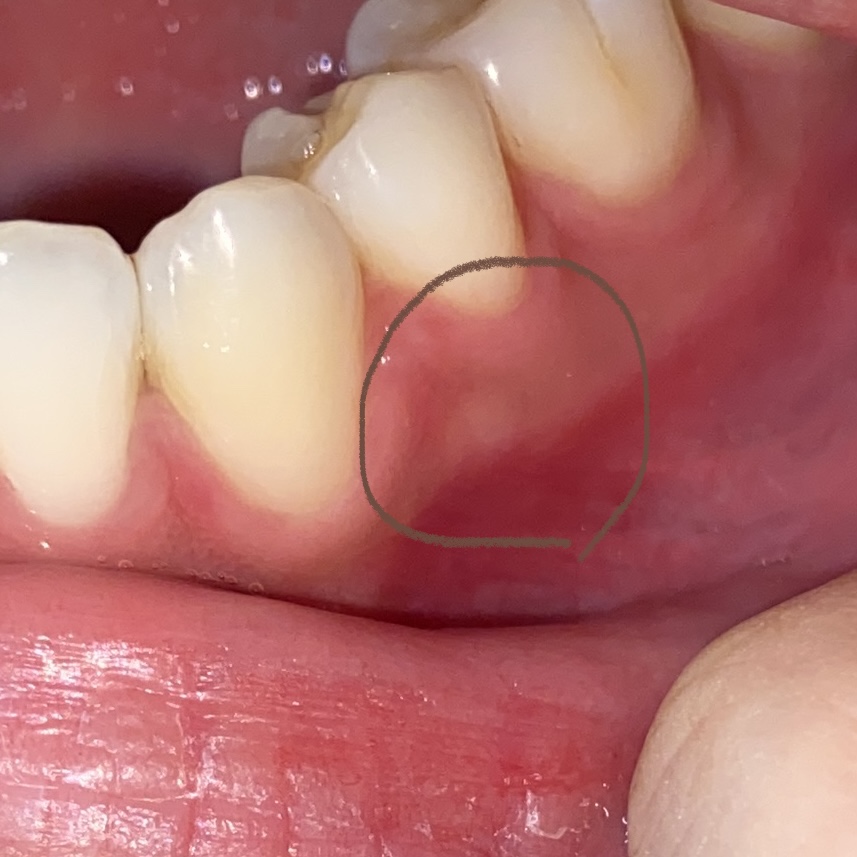

염증 위 치아에 충치는 없나요?

충치가 깊어져 신경까지 염증이 심해지면

저렇게 잇몸이 붓고 피나고 곪기도 하더라구요

타이레놀은 소염효과가 없어요

타이레놀은 아세트아미노펜이 주성분인데 이건 해열 진통효과만 있거든요.

물론 진통효과가 있으니 당장에 통증은 줄일 수 있죠.

소염 효과를 기대하신다면 브루펜계열의 덱시부프로펜이나 이부프로펜 진통제를 복용하셔야 하는데

소염 진통 해열에 효과적이기때문에 통증도 잡고 염증도 줄여줄겁니다

다만 당장에 염증을 조금 줄여주는거지 절대 치료하는게 아니에요